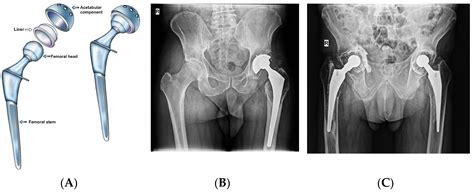

Gathering this information helps your doctor understand the functional impact the pain has on your life. Be prepared to discuss your medical history, any past injuries, and previous attempts at conservative treatment. Your surgeon will typically order X-rays to visualize the joint space and assess the degree of bone-on-bone contact or deformity.

Modern surgical techniques have significantly advanced, making hip replacement one of the most successful orthopedic procedures. While the idea of surgery can be daunting, the primary goal of the procedure is to relieve pain and improve your ability to function. After surgery, patients typically begin physical therapy almost immediately, focusing on strengthening the muscles around the new joint to support long-term stability and mobility.